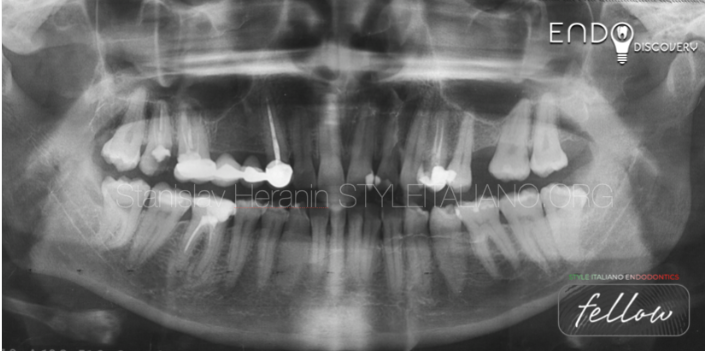

上图1:一名32岁患者因需根管再治疗转诊至我科

患者自述既往有多次根管治疗史。46牙存在旧的MOD复合树脂充填体破损。颊侧可见瘘管。诊断性X线片显示46牙根尖及根分叉区域透射影(怀疑穿孔)。叩诊无痛,牙周探诊在正常范围内。治疗计划为使用MTA进行非手术根管再治疗并修复穿孔。

初诊影像:全景X线片转诊患者:V.,32岁,女性诊断:46慢性根尖周炎根分叉穿孔 瘘管